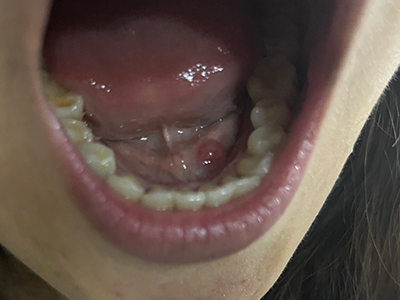

舌下腺囊肿舌底下长了个蚕豆大小的疙瘩图

舌下腺囊肿出现在舌系带一侧,表现为凸出于黏膜表面的疙瘩,如蚕豆大小,质地较软,有异物感,局部自发破溃,流蛋清样液体,常反复出现。